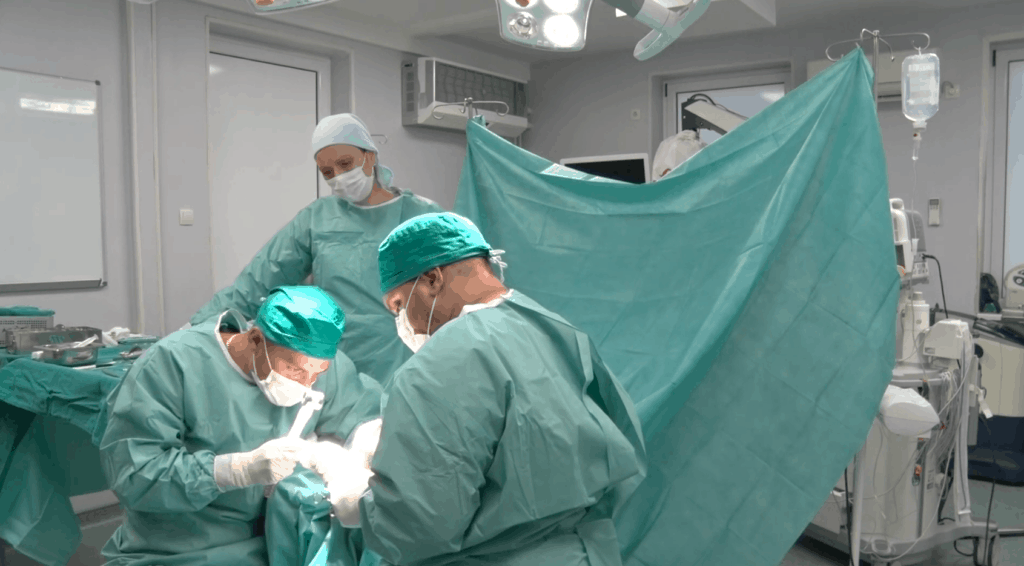

Dr. Branislav Krivokapić: “ With this patient, we decided to perform a Chevron osteotomy of the first metatarsal bone-the joint of the first metatarsal bone. It is the ankle of the big toe that we moved inwards to return the big toe to the shaft. Of course, we loosened the tendons that pull the finger out so that it stays in that position after the operation. ”